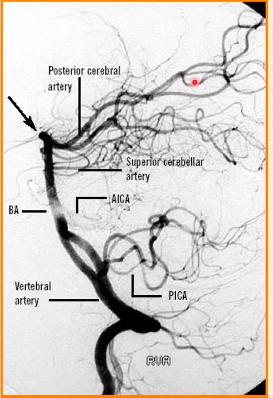

label A-D [4]

A: vertebral artery

B: superior cerebellar artery

C: posterior cerebral artery

D: basilar artery

which artery provides blood to the midbrain & thalamus

PICA

AICA

superior cerebllar artery

pons

posterior cerebral artery

which artery provides blood to the dorsal medullar of midbrain?

posterior spinal arteries come off which arteries? [1]